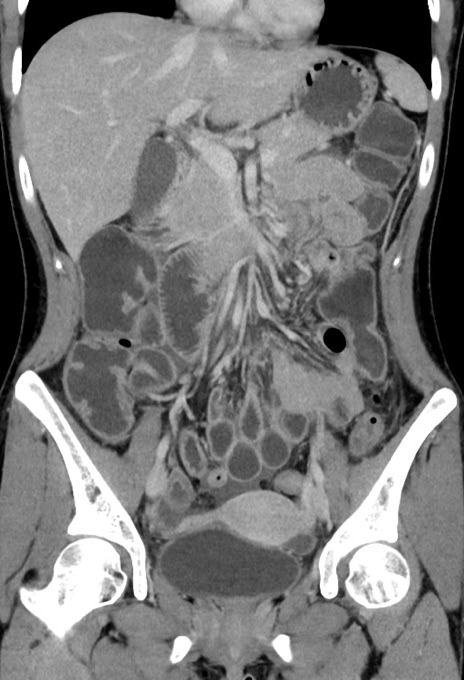

横断像

【症例】20歳代女性

【主訴】嘔吐、下腹部痛

【現病歴】昨日夕食後に嘔吐し下腹部痛が出現。本日になっても嘔吐持続し改善しないため来院。

【身体所見】意識清明、BT 37.2℃、BP 108/67mmHg、腹部:平坦、やや硬、下腹部正中から右にかけて圧痛あり、反跳痛軽度あり、tapping pain(+)。

【データ】WBC 13600、CRP 14.94